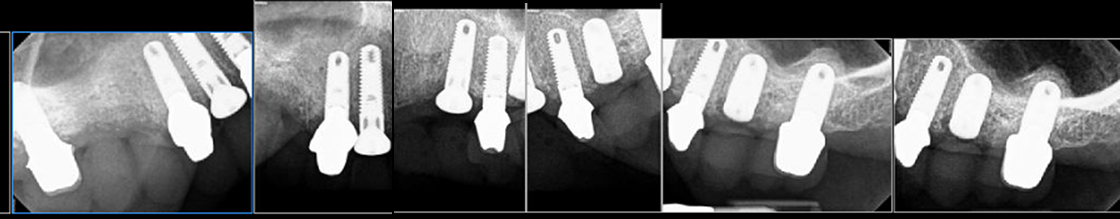

When all of a patient’s teeth are failing but dentures aren’t an option, we perform “staged therapy.” First, every tooth is prepared and fitted with a full-arch temporary splint (Fig. 1). Next, select teeth are extracted and replaced with implants, while the remaining teeth continue to hold the temporary (Fig. 2 & 3). In Stage II, abutments are seated on existing implants, the remaining teeth are extracted, and implants placed (Fig. 4). Finally, a permanent fixed splint is secured on all implants (Figs. 5 & 6).

Fig. 4: Stage II Abutments Seated in Implants to Hold the Temporary, Remaining Teeth Extracted and Replaced

Stage II: Previously inserted implants have abutments inserted and connected to the temporary splint (Fig. 4). The remaining teeth are then extracted with implants replacing them.